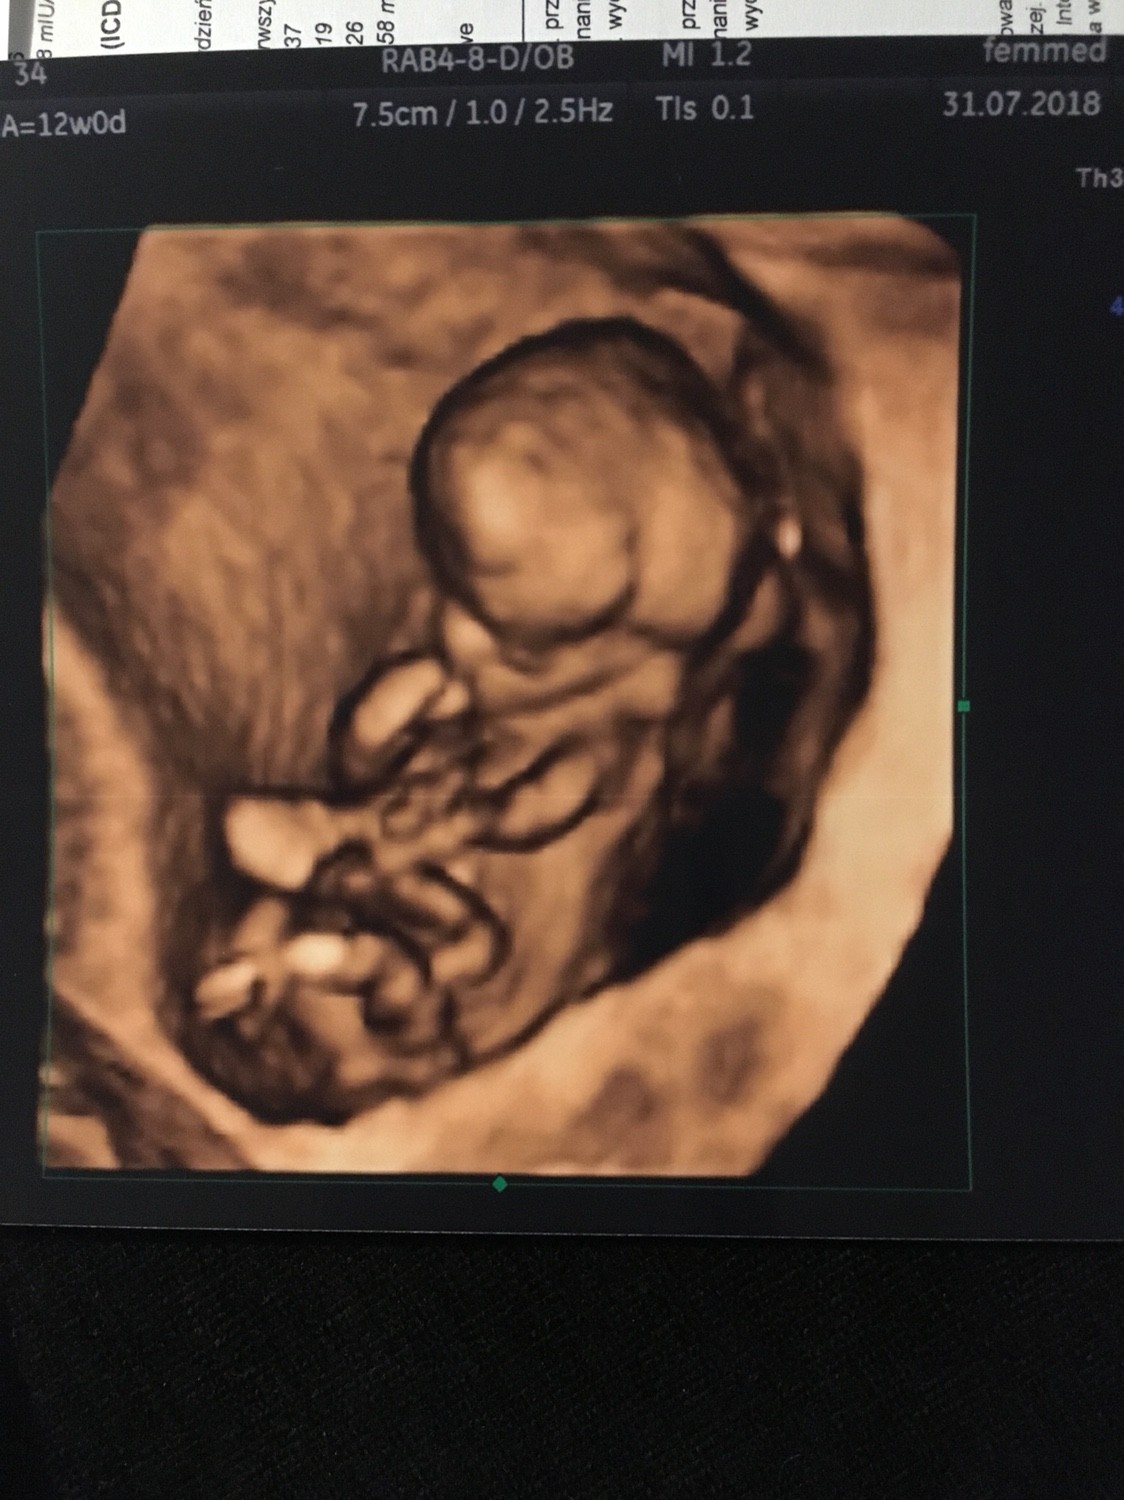

Wszystko ok z maluchem, nawet bardzo ok wg lekarza [emoji846]

Dzidź ma 60,2 mm i serduszko puka 160/min [emoji846] Kość nosowa uwidoczniona, przezierność 1,5 mm i na podstawie usg o 2 dni straszy niż wg om. Jeśli chodzi o wyniki testu zintegrowanego to skorygowane ryzyko dla trisomii 21 wynosi 1:6491, dla trisomii 18. 1:15576 a dla trisomii 13 jest <1:20000

Ulżyło mi baaaaardzo i jestem przeszczęśliwa [emoji846]

Maluch cały czas się wiercił i ruszał [emoji846]

Zobacz załącznik 883462